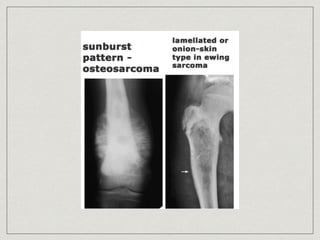

mottled destruction containing lytic and blastic area, onion skin

appearance

Osteosarcoma

bone destruction with indistinct borders merge into

adjacent normal bone, sunbrust appearance

Ewing’s sarcoma small roundcell sarcoma 15% presented at chest wall, 17% all primary chest wall tumor age >40 years old, male x2> female painfull, enlarging mass associated with fever, malaise, leukocytosis, anemia, increase ESR mottled destruction containing lytic and blastic area, onion skin appearance medical treatment, surgical role to biopsy 5-year survival 48%

Osteosarcoma 10% of allprimary chest wall tumor, poor prognosis teenagers, and young adults rapidly enlarging, painful mass, high ALP bone destruction with indistinct borders merge into adjacent normal bone, sunbrust appearance chemotherapy with wide resection 5-year survival 15%